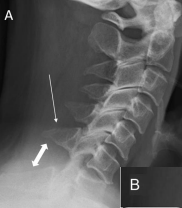

Hangman’s Fx

Extreme hyperextension, resulting in fx that extends through the pedicles of C2, with or without anterior displacement of C2 on C3

Immb. or surgery

A patient with a hangman's fracture is not stable because the intact ____ is pressed posteriorly against the ____.

Odontoid

Brain stem

Hangman's fracture is best demonstrated on ____.

Lateral C-Spine